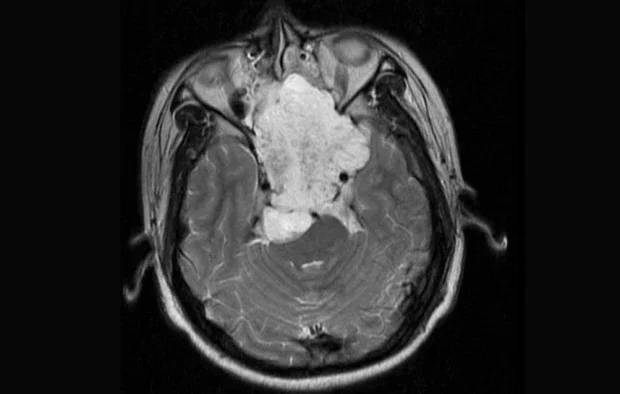

- образни изследвания: образните методи са водещи за първоначалното откриване и стадиране на тумора. Ядрено-магнитен резонанс се счита за златен стандарт за оценка на хордом, като позволява прецизна визуализация на размера и разпространението на тумора, наличие на инфилтрацията в меки тъкани, засягането на нервни структури и гръбначния мозък. Компютърната томография е особено полезна за оценка на костната деструкция, планиране на хирургичното лечение и разграничаване от други костни тумори

ЯМР на обширен хордом на кливуса при 17-годишен пациент, аксиален изглед. Туморът в назофаринкса, простиращ се от носната кухина до мозъчния ствол, е ясно видим. Изображение: Hassan S, Abdullah JM, Wan Din SJ, Idris Z , Лиценз CC BY 2.0, чрез Wikimedia Commons